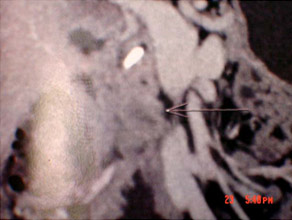

CT scan of Chronic pancreatitis with cancer (stent seen in the pancreatic duct, arrow pointing the tumor)